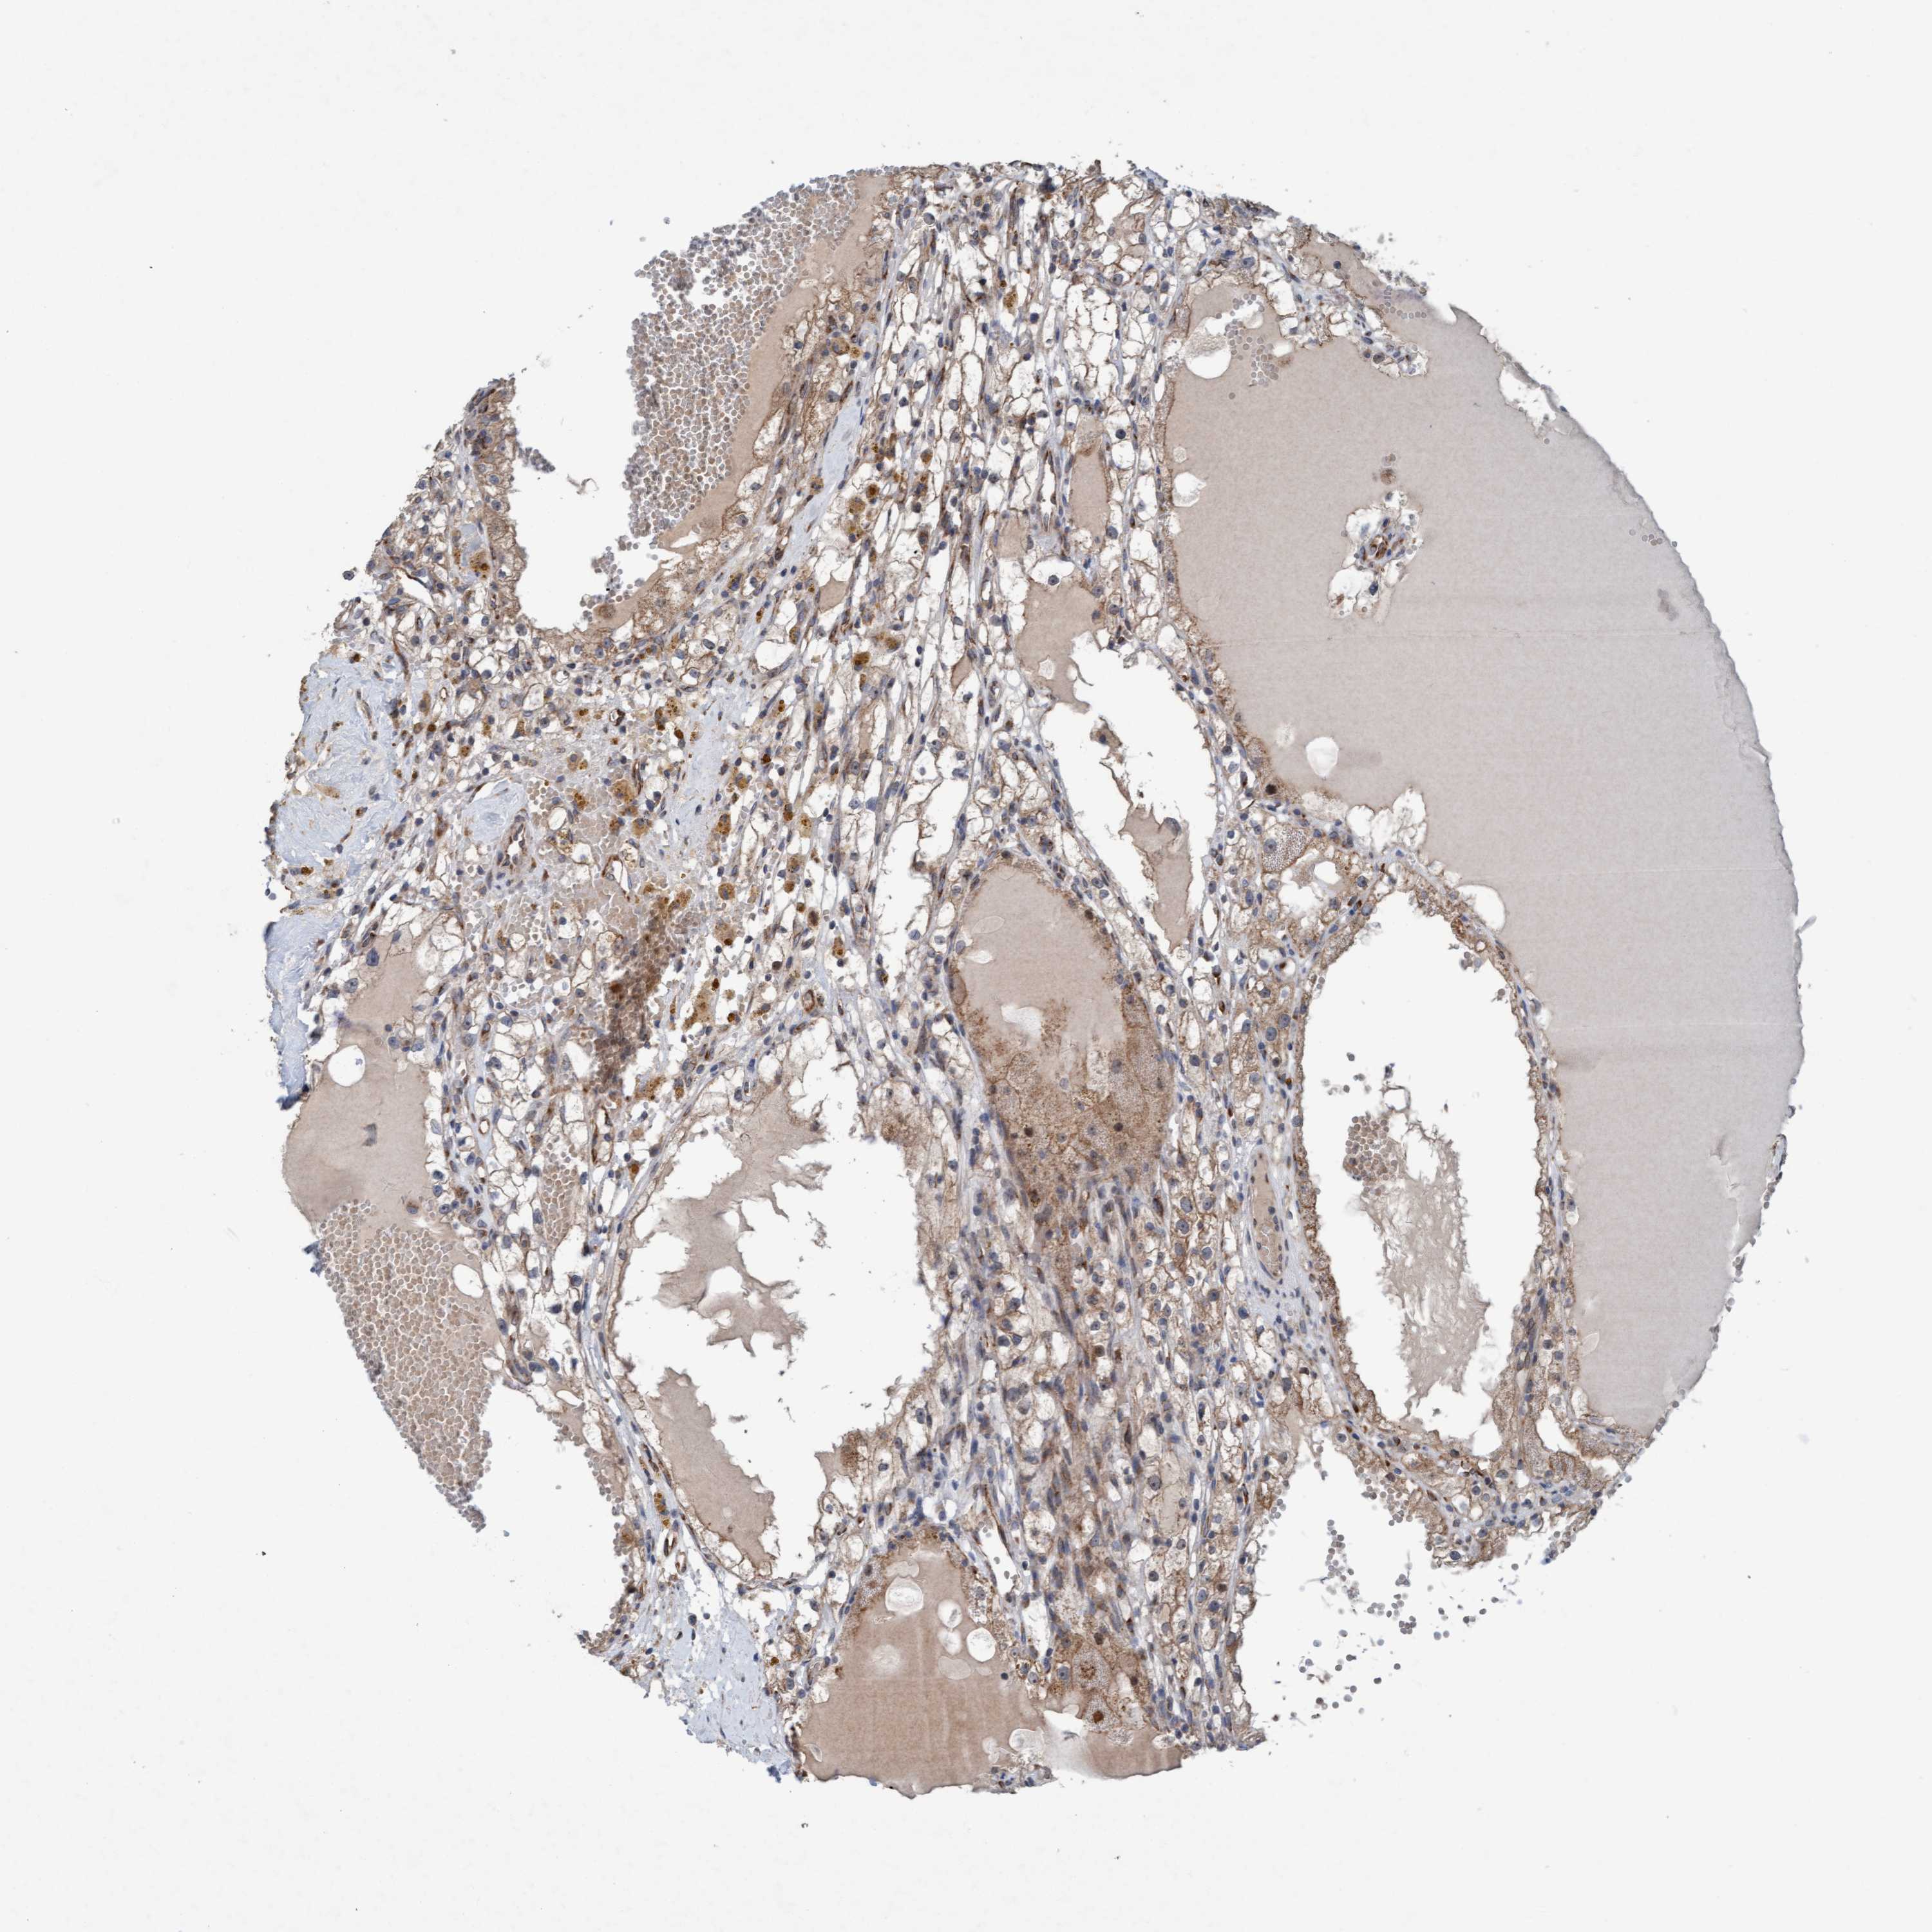

KIDNEY RENAL PAPILLARY CELL CARCINOMA (TCGA) - Interactive survival scatter ploti

The Survival Scatter plot shows the clinical status (i.e. dead or alive) for all individuals in the patient cohort, based on the same data that underlies the corresponding Kaplan-Meier plots. Patients that are alive at last time for follow-up are shown in blue and patients who have died during the study are shown in red.

The x-axis shows the expression levels (FPKM) of the investigated gene in the tumor tissue at the time of diagnosis. The y-axis shows the follow-up time after diagnosis (years). Both axes are complimented with kernel density curves demonstrating the data density over the axes. The top density plot shows the expression levels (FPKM) distribution among dead (red) and alive patients (blue). The right density plot shows the data density of the survived years of dead patients with high and low expression levels respectively, stratified using the cutoff indicated by the vertical dashed line through the Survival Scatter plot. This cutoff is automatically defined based on the FPKM cutoff that minimizes the p-score. The cutoff can be changed by dragging the vertical line or by entering a cutoff value in the square labeled "Current cut-off".

Under the Survival Scatter plot the p-score landscape (black curve; left axis) is shown together with dead median separation (red curve; right axis). Dead median separation is the difference in median mRNA expression between patients who have died with high and low expression, respectively. It is calculated as follows: median FPKM expression of dead patients with high expression - median FPKM expression of dead patients with low expression. This is intended to aid the user in visually exploring custom cutoffs and the associated p-scores and dead median separation.

Individual patient data is displayed and can be filtered by clicking on one or more of the category buttons on the top of the page. Categories describing expression level and patient information include: high, low, alive, dead, female, male and tumor stages. The scale of the x-axis can be toggled between linear and log-scale by clicking on the "x log" button. Mouse-over function shows TCGA ID, patient information and mRNA expression (FPKM) for each patient.

& Survival analysisi

Kaplan-Meier plots summarize results from analysis of correlation between mRNA expression level and patient survival. Patients were divided based on level of expression into one of the two groups "low" (under cut off) or "high" (over cut off). X-axis shows time for survival (years) and y-axis shows the probability of survival, where 1.0 corresponds to 100 percent.

ZNF566 is not prognostic in Kidney Renal Papillary Cell Carcinoma (TCGA)

Best expression cut offi

Based on the FPKM value of each gene, patients were classified into two groups and association between prognosis (survival) and gene expression (FPKM) was examined. The best expression cut-off refers the FPKM value that yields maximal difference with regard to survival between the two groups at the lowest log-rank P-value. Best expression cut-off was selected based on survival analysis .

When clicking on this number, the vertical dashed line indicating cut-off, the interactive survival plot, and the Kaplan-Meier curve will be adjusted to show results based on the best expression cut-off.

: 2.25